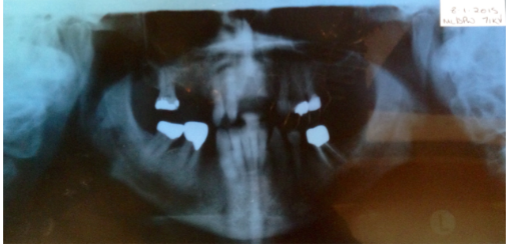

Case Title: Implant placement next to a peri apically infected site

• Peri-apical lesion UR1 seen on radiograph

• RCT carried out 10 years ago

• Asymptomatic

• No clinical signs

CBCT scan OF UR1 Site, peri-apical cyst?